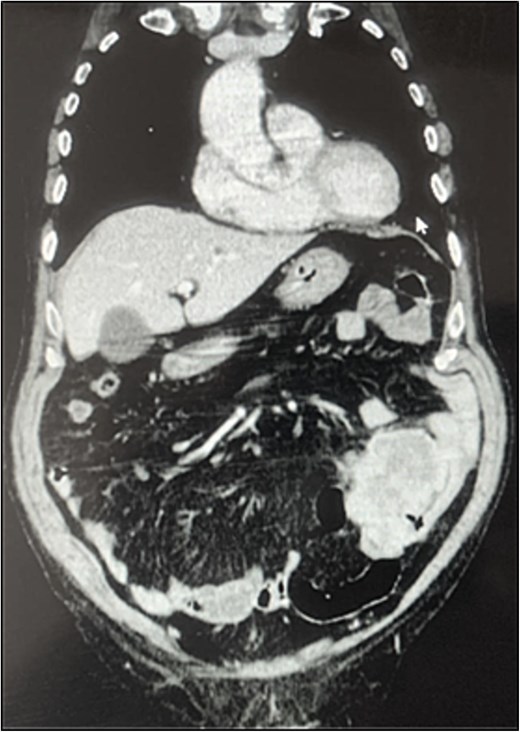

A contrast-enhanced chest-abdominal-pelvic computed tomography (CT) scan revealed a solid, multilobular mass, with approximately 8 × 6 × 8 cm, likely originating from the SB, with asymmetric wall thickening, heterogeneous contrast enhancement, areas consistent with necrosis and central calcification (Figs 1 and 2), suggestive of GIST. Simultaneously, a solid nodular lesion was identified on the anterior wall of the rectum, exhibiting exophytic growth with a heterogeneous texture, well-defined borders and measuring 5 × 3 cm, without adjacent fat infiltration, raising suspicion of another GIST (Fig. 3).